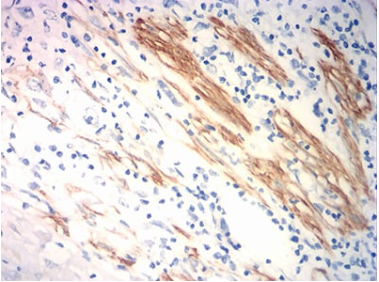

ACTA2 Mouse Monoclonal antibody[8D8B4]

IHC    1/200 - 1/1000